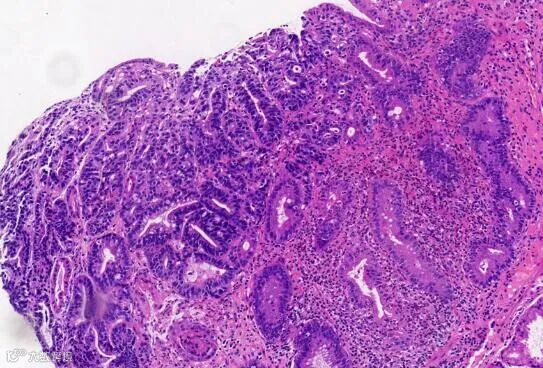

瑞氏试剂中酸性伊红和碱性美蓝混合经化学作用后,变成中性的伊红化美蓝,久置后,经氧化而含有天青。此三种染料分别和细胞中的NH3+和COO-等结合,使细胞核及胞浆着色。由于系中性染料,又有缓冲液调节酸碱度,所以细胞受染后,蓝红等颜色都较适中,核染质、胞浆以及其中颗粒显色较为清楚。 |

病理学以及疾病研究中常用的染色剂。染色原理和结果与瑞氏染色法基本相同。但该法对细胞核和寄生虫着色较好,结构显示更清晰,而细胞质和中性颗粒则着色较差。为兼顾二者之长,可用复合染色法。 |